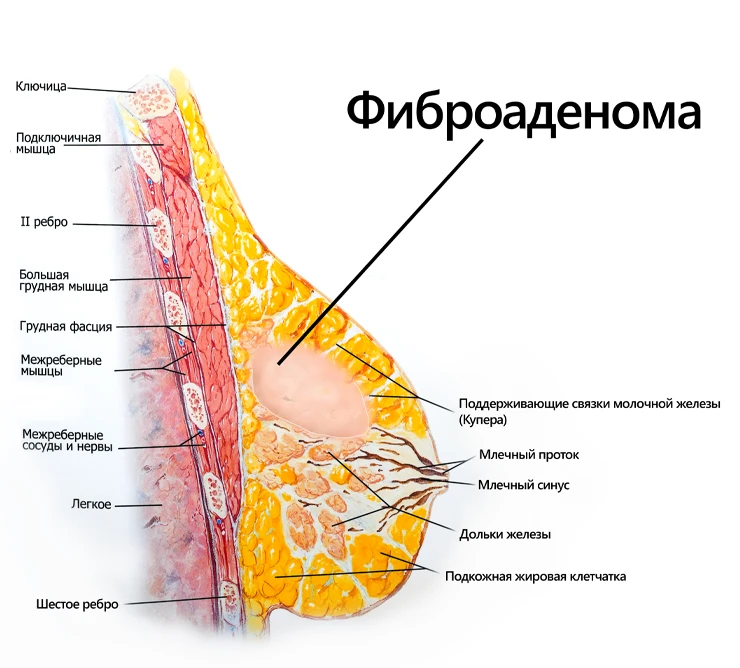

Аномалии молочной железы: медицинские примеры и визуализация

Раздел: Мудрость в деталях